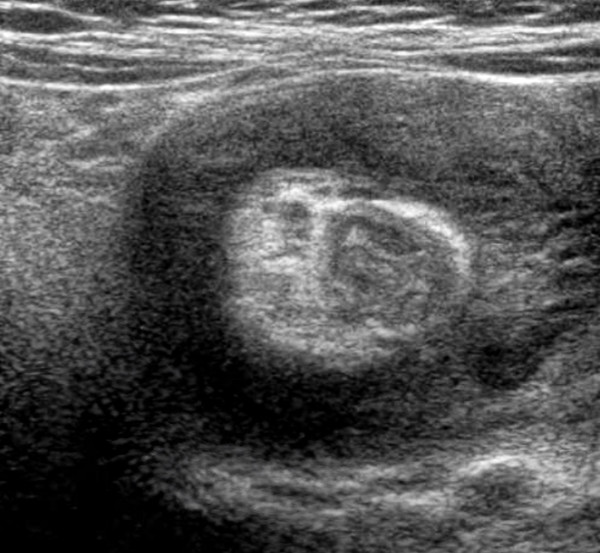

진단을 위해 가장 먼저 복부 X선 촬영을 시행한다. 이를 통해 장관 내의 가스 분포를 확인하거나, 만져지는 종괴의 음영을 확인하여 장중첩증을 의심할 수 있다. 이후, 복부 초음파로 “도넛 사인”과 같은 특징적인 소견을 통해 정확한 진단을 할 수 있는데 장이 말려 들어가 겹쳐진 모양의 단면이 마치 도넛 모양으로 보이기 때문이다.